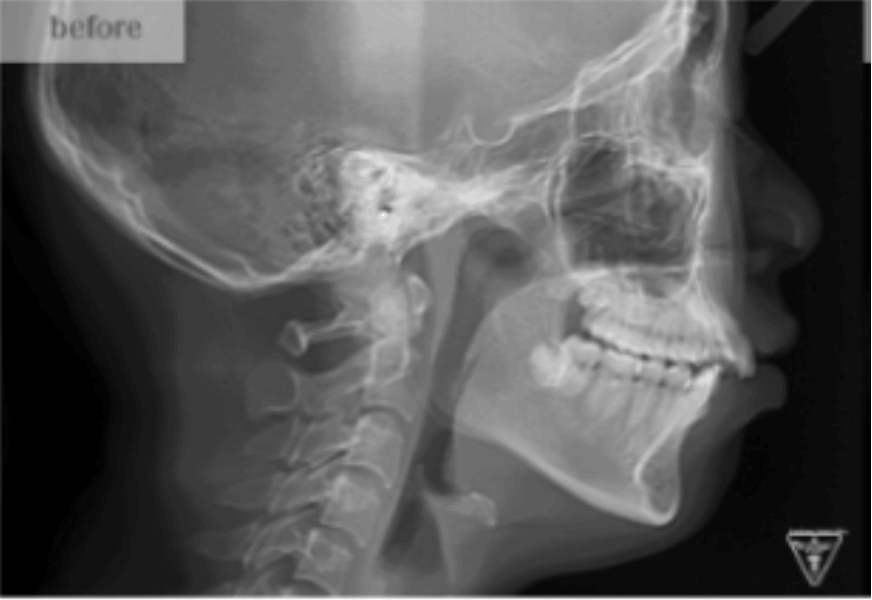

治療前

治療前後の比較

10代女性:矯正治療